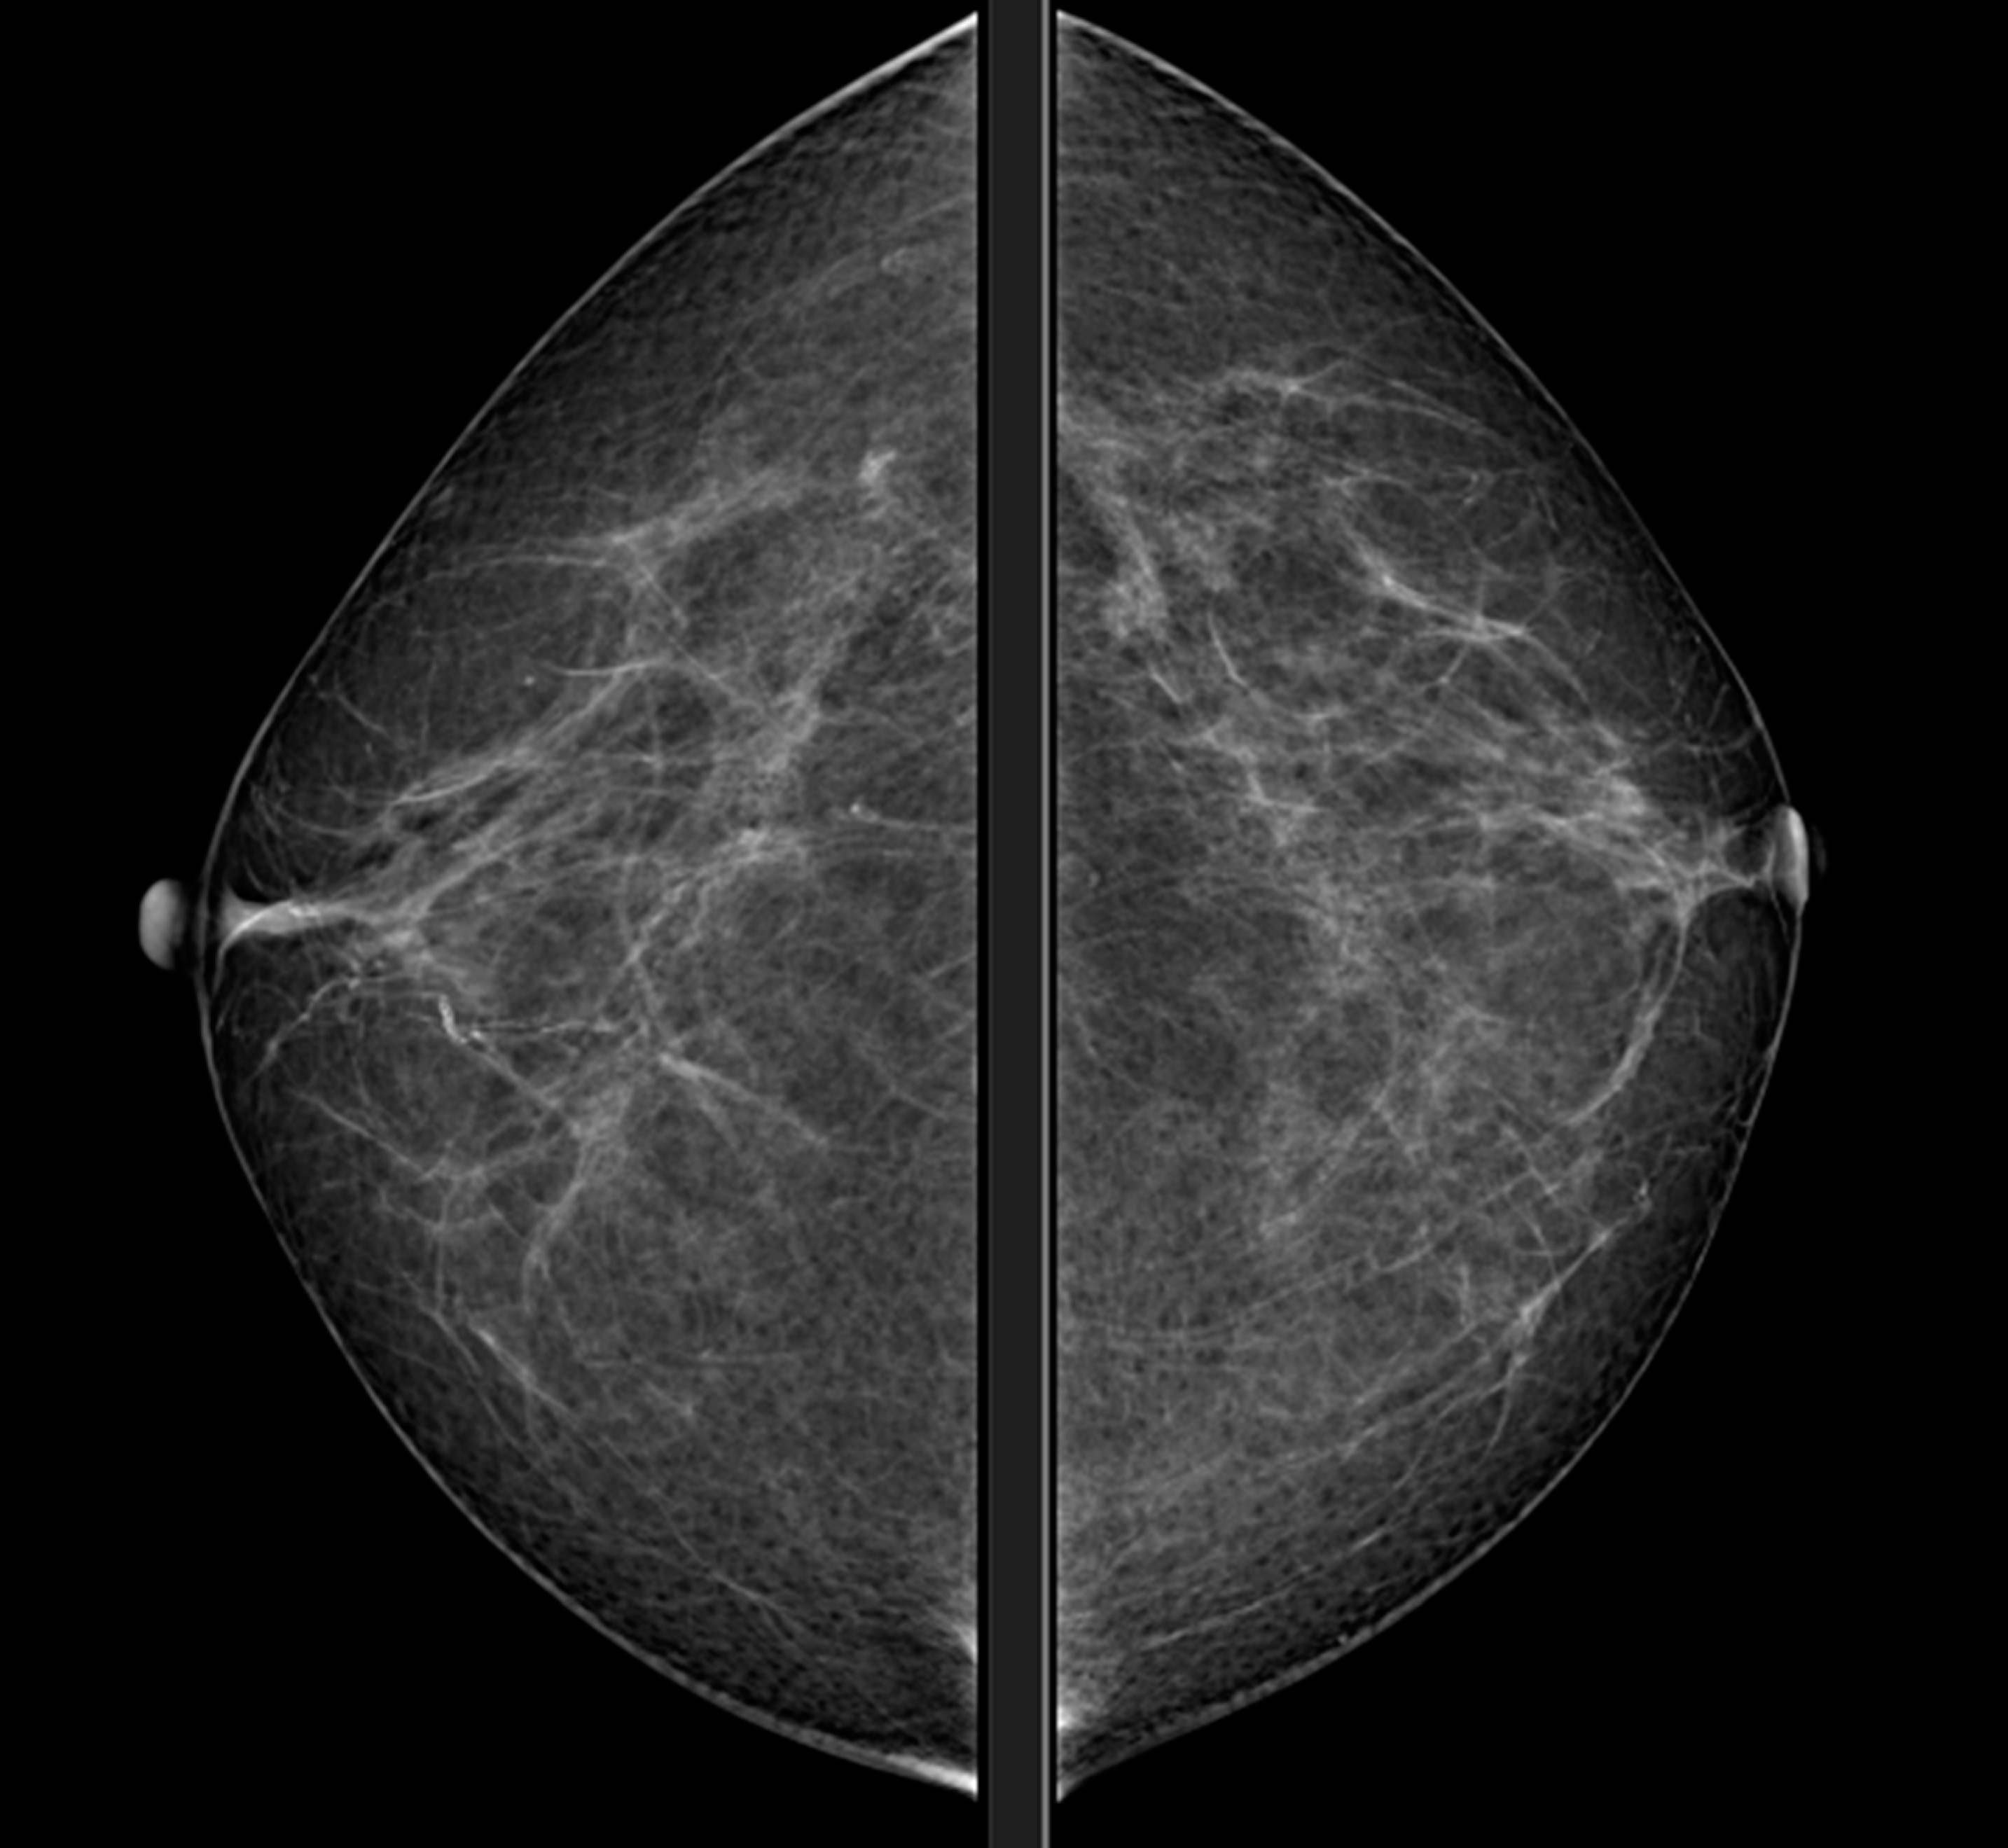

Mammography

MAMMOGRAPHY